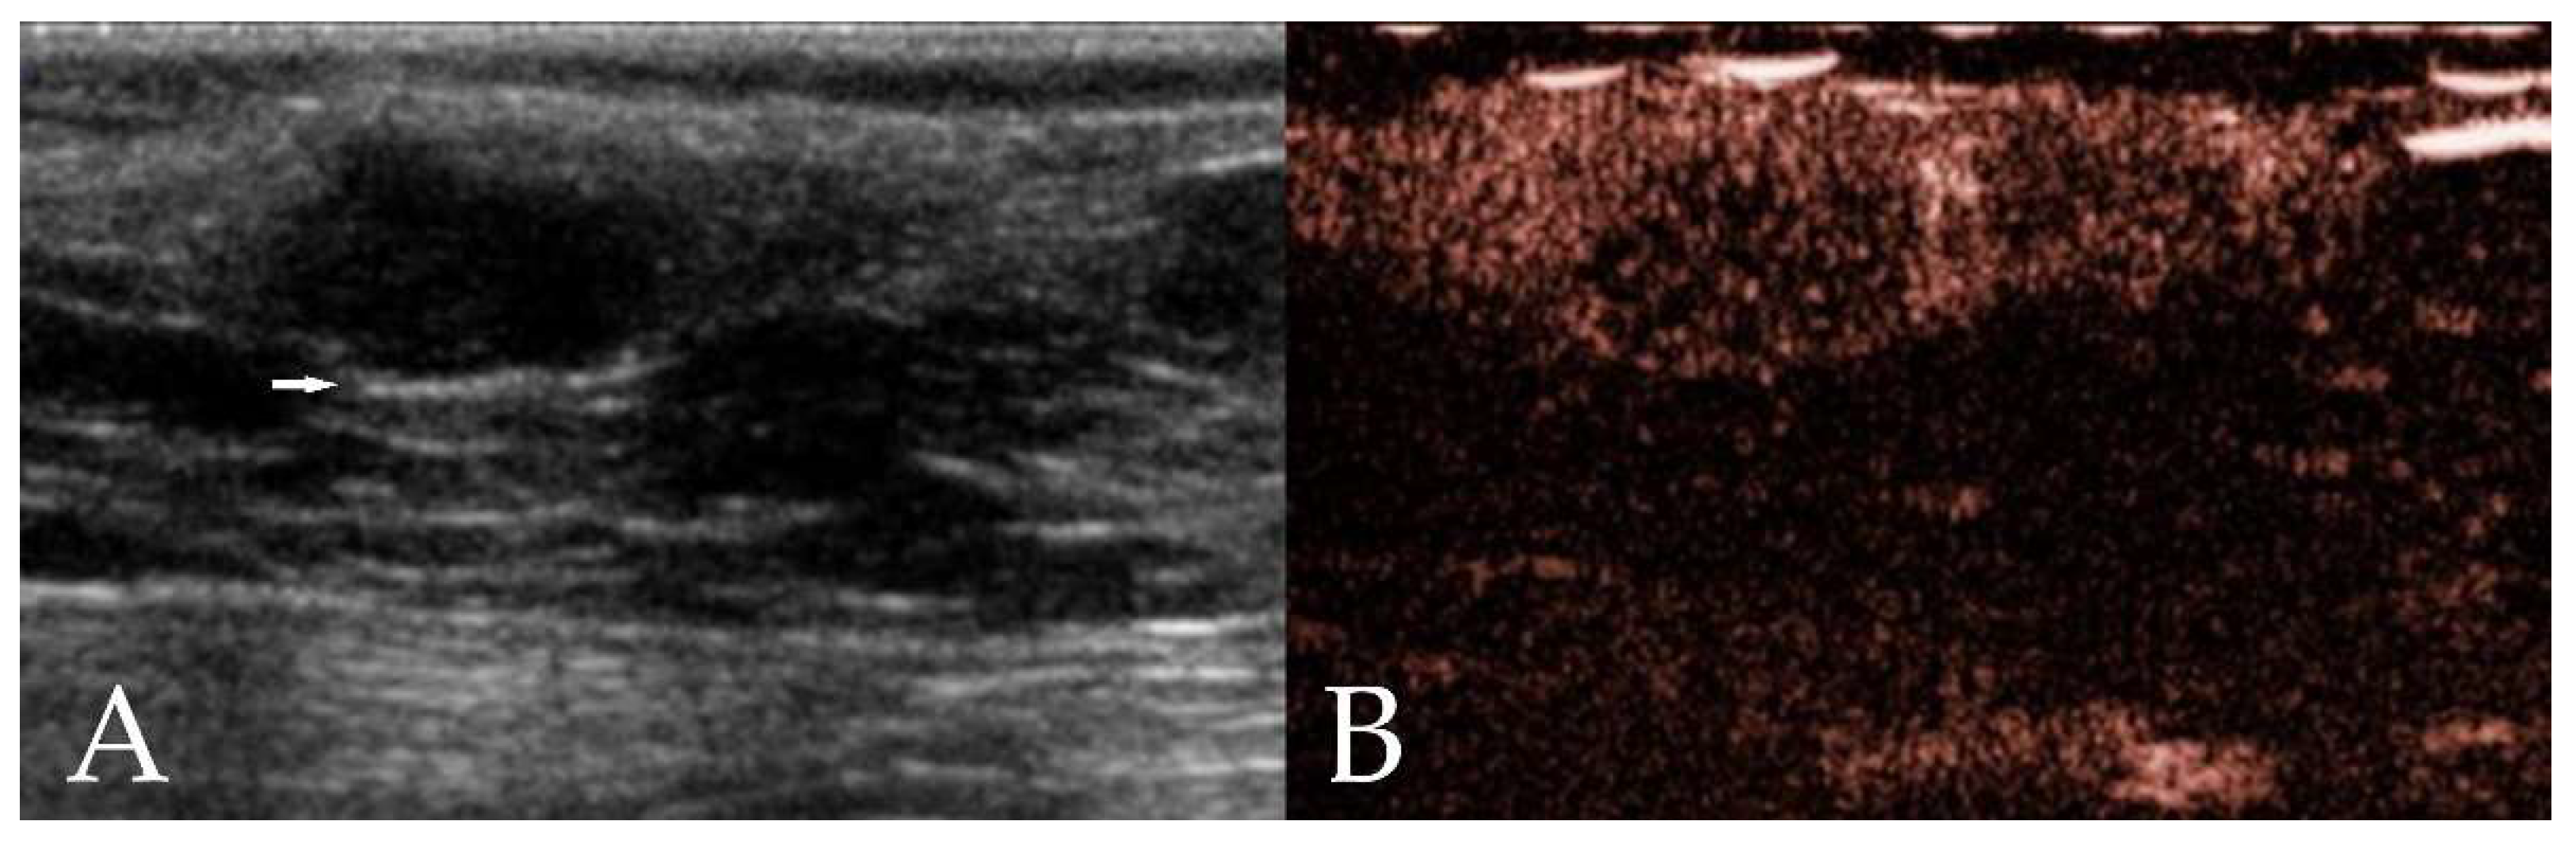

3.2.1. B-Mode Ultrasound

3.2.2. Qualitative CEUS